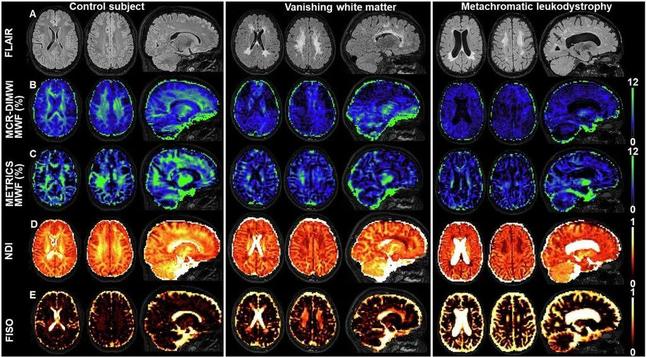

Join Loukas G. Astrakas as he dives into the future of leukodystrophy diagnosis, exploring the potential of new techniques, including quantitative MRI (qMRI). Could the integration of qMRI improve our diagnosis, monitoring, and treatment of patients with leukodystrophies?

Commentary πŸ‘‰ rdcu.be/d00eZ

Original Article πŸ‘‰ buff.ly/3U4UrCj